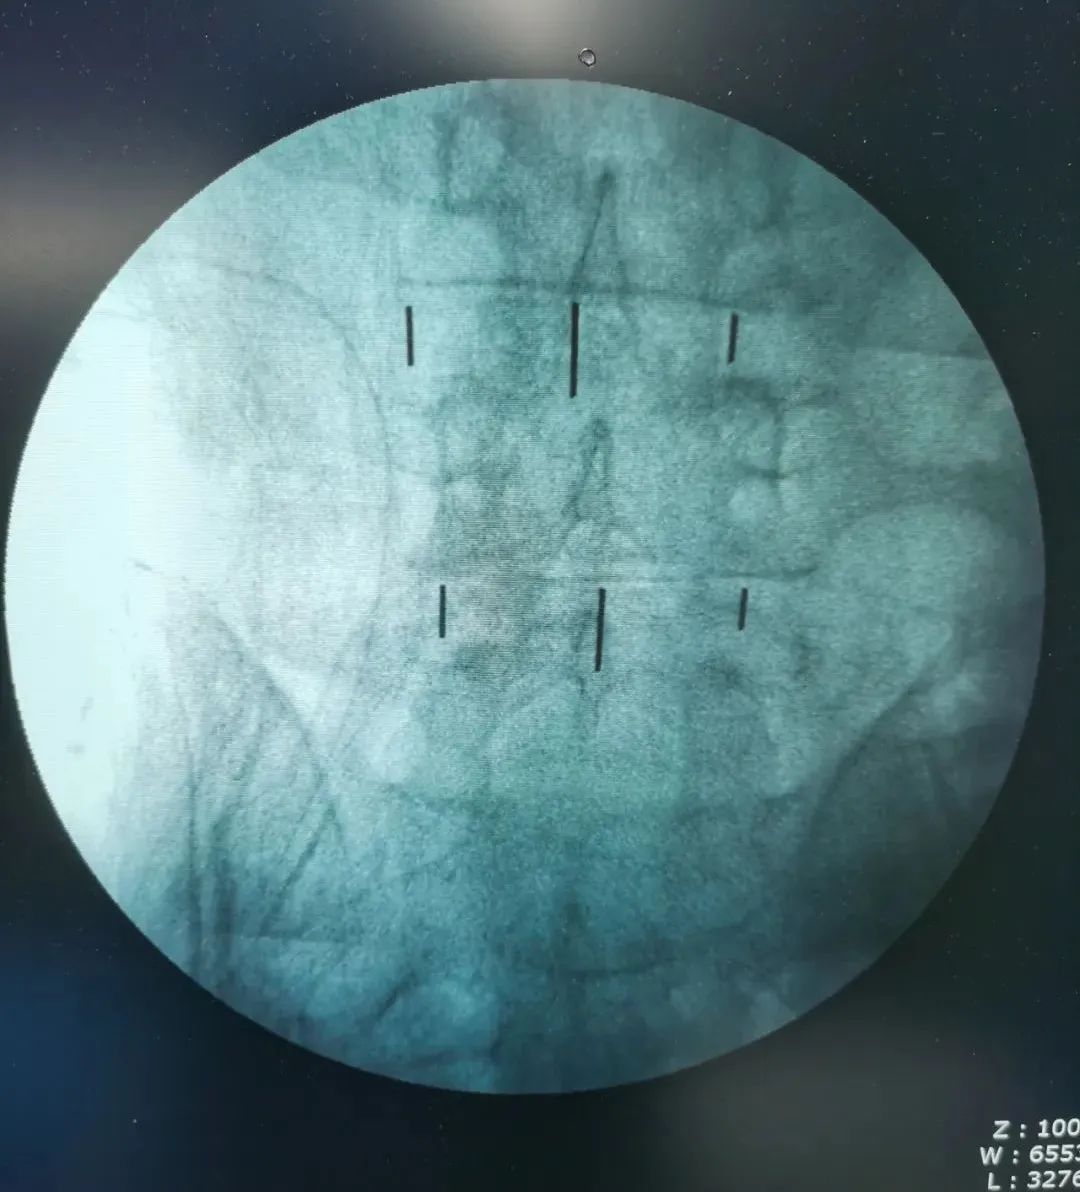

▲术中影像

经过周密细致地术前讨论及评估,由张少华主任主刀,熊东医生、手术室(麻醉科)默契配合,为李先生成功实施“OLIF腰椎微创椎体间融合术”,目的:减压,复位,融合;术中操作干净利落、精准微创,顺利完成,手术历时近4小时。